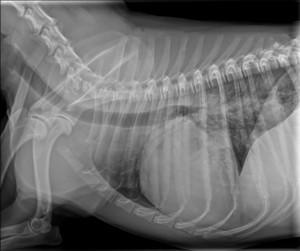

Kadar veterinar pri tem posumi na bolezen srca, je potreben celosten pregled kardiovaskularnega sistema, ki ga opravi veterinar – kardiolog. Ta večinoma obsega klinični pregled, ultrazvok srca, EKG in ob sumu na dekompenzacijo rentgen pljuč. To nam omogoči postavitev natančne diagnoze, ki je ključnega pomena za uspešnost terapije in dolgoročno prognozo.

Omenjene bolezni so le ene od tistih, s katerimi se srečujemo veterinarski kardiologi; seveda pa je srčnih obolenj še veliko več. Za uspešnost zdravljenja je največjega pomena natančna diagnoza. Te si v današnji veterinarski kardiologiji, ki v mnogih stvareh sledi humani medicini, ne moremo več predstavljati brez specialističnih preiskav. Sem sodi na prvem mestu ultrazvočna preiskava srca, ki je za postavitev diagnoze nepogrešljiva. Za celostno sliko obolenja pa večinoma potrebujemo še dodatne preiskave, kot so rentgensko slikanje pljuč, elektro kardiološka preiskava srčnega ritma, merjenje krvnega tlaka. Terapijo je nato potrebno natančno prilagoditi potrebam posameznega pacienta, saj se na zdravila ne odzovejo vsi enako. Tu je izjemnega pomena tesno sodelovanje in zaupanje med skrbnikom psa in izbranim veterinarjem – kardiologom. Le na tak način si zagotovimo optimalno kontrolo bolezni ter zadovoljstvo vseh: živali, njihovih skrbnikov ter ne nazadnje nas, kardiologov.